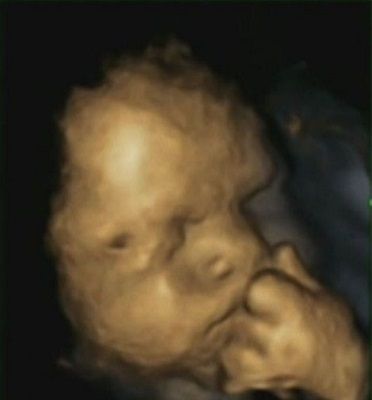

扫描图像显示,准妈妈焦虑时,她们腹中的宝宝也愁眉紧锁,并用手触碰脸部。东方网6月4日消息:准妈妈会不会和自己腹中的宝宝有“心灵感应”?英国一项研究显示,如果准妈妈焦虑,腹中的宝宝也能“感同身受”。而且宝宝在感到焦虑时,还会用小手触摸脸部,缓解压力。

据英国媒体报道,英国杜伦大学的一项研究为孕妇进行4D超声波扫描,研究发现,当母亲感到焦虑时,胎儿摸脸的次数会增加。研究人员为15名孕妇进行了4次4D超声波扫描,同时录制影片,并向孕妇们询问她们在一个月内的压力水平。

研究结果发现,15名孕妇所怀的8名女婴及7名男婴共摸脸342次,当母亲感到焦虑不安、无助或压力大时,胎儿便越发愁眉苦脸,并会用左手触摸自己的脸。